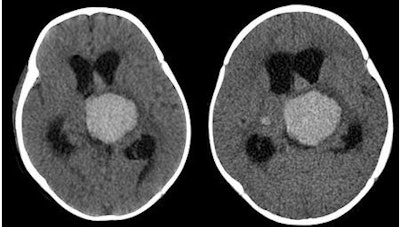

| Images are of a 7-month-old female with parenchymal and intraventricular hemorrhage. Left, portable CT; right, standard MDCT. Images courtesy of Children's Healthcare of Atlanta at Egleston, Department of Radiology. |

"All images from the portable CT scanner were diagnostically acceptable," Udayasankar said. "Both groups of images had an average rank of 3 with respect to image quality and 4 for diagnostic acceptability. While image noise was slightly greater with the portable unit, there was no significant perceived difference in image quality obtained from the portable and stationary scanners."